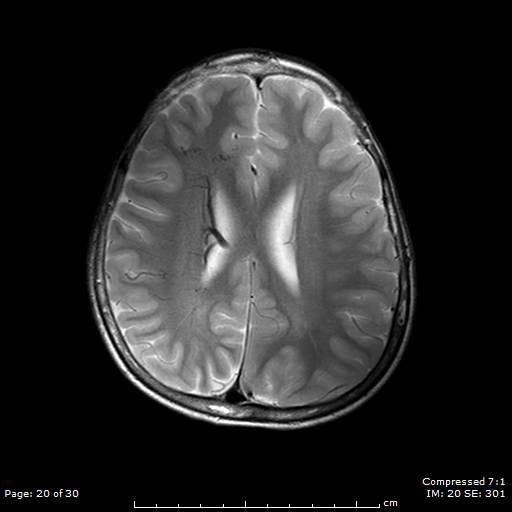

Patients suspected of SWS will have a CT or MRI scan. This will now typically be done if the patient is seen to have a Port-Wine Stain in the V1 distribution to assess for associated involvement in the brain.

The image above shows an example of what an MRI (top) and a CT scan (bottom) would look like in a patient with SWS. In the CT scan on the left side, you can see this white mark. This is caused by a process known as calcification where deposits of calcium phosphate build up in the brain, creating ‘brain stones’ that can increase in size, and potentially induce further neurological issues. In addition, you are also able to observe the size difference from the left to the right of the brain. This is known as brain atrophy. Both calcification and extent of brain atrophy are key factors in determining the severity of the neurological conditions in SWS. Emerging research by Great Ormond Street Hospital proposed targeting these abnormally high inter-cranial calcium deposits as a potential therapeutic pathways to reduce progression of cortical damage.